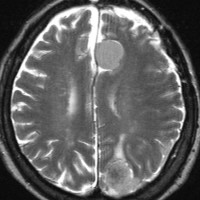

片側髄膜腫症 unilateral meningiomatosis

50歳ころから15年間に3回の開頭手術を受けている患者さんです。parasagittal, falx, convexityなど6個の髄膜腫がすでに摘出されています。左側だけ,テント上だけに髄膜腫が20個くらい多発していました。これらはグレード1で,anaplastic meningiomaの転移ではありません。

やがて蝶形骨縁の髄膜腫の増大速度が早まりatypical meningiomaとなりました。MIB-1 index が10%の高値でした。病理学的にも,psamomatous meningiomaなど様々な種類の髄膜腫が多発しています。